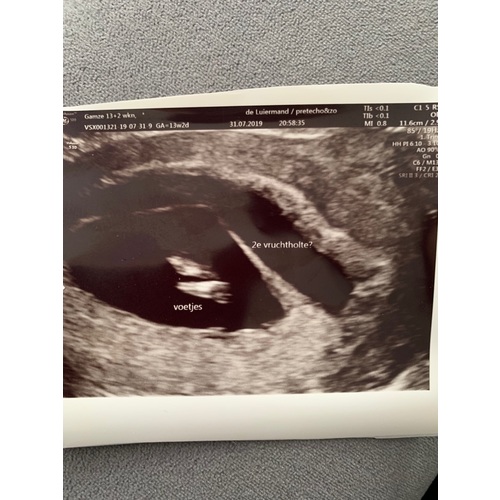

Hey had het ook tijdens me zwangerschap bij het pretecho er achter gekomen , gelijk de vk gebeld en met spoed doorgestuurd naar zk , ze wisten niet wat het was heb veel stolsels verloren tot week 29+4 gebloed moest bedrust nemen en geen huishoudelijke taken verichten .. trouwens met 31 weken was her verdwenen gelukkig , heb nu een zoontje van 3 maanden .